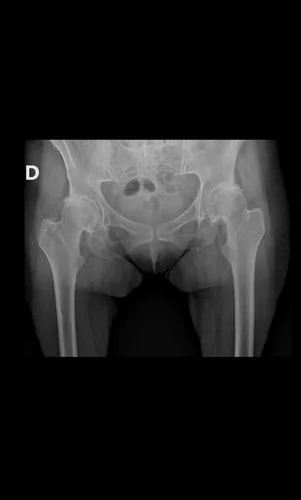

Preoperatorio

Postoperatorio

Artroplastia bilateral simultánea con utilización de tallo femoral acortado (short stem). Esta opción preserva mayor stock óseo y facilita una fijación biológica óptima. Alta a las 24 horas caminando con andador.